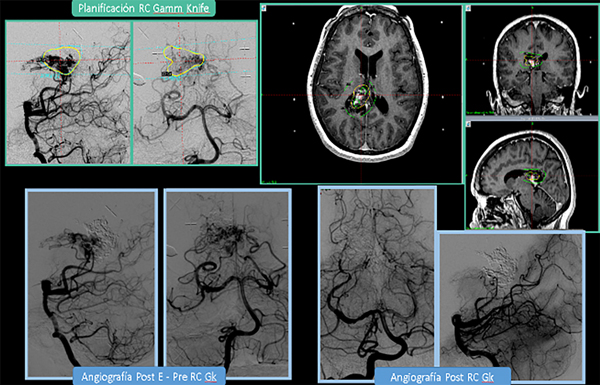

Para las lesiones Grado III “pequeñas” en área elocuente y con drenaje venoso, es decir, las tipo “3–” de Lawton o tipo “B” de Oliveira se indica RC o tratamiento combinado (“E + RC” si el volumen sobrepasa el que es posible tratar de forma segura) (Ver Figura 3). Para las Grado III intermedias incidentales, entre 3 y 6 cm, en área elocuente (o tipo “3 +” de Lawton) se prefiere un manejo conservador; si posee “factor de riesgo angiográfico de ruptura”, un tratamiento multimodal (“E + RC”). En las Grado III intermedias con drenaje venoso profundo (“3”de Lawton) se propone un tratamiento multimodal combinado: “E+ RC”, Vs “E+MC” Vs “RC fraccionada”(Staged o Repeated). En los casos de Grado III únicamente por volumen ( 7 cm, área no elocuente, sin drenaje venoso profundo) sopesar observación vs E+MC según comité de expertos multidisciplinario.

Figura 3: Paciente con MAV SM Grado III: (<3 cm, A. Elocuente + y drenaje venoso profundo +). “3-“ Lawton o “B” Oliveira. A pesar de ser <3cm, el volumen era intermedio. Fue embolizada, y posteriormente tratada con Radiocirugía Gamma Knife (GK). Planificación de GK: A) angiografía estereotáxica. B) RM cerebral del día del tratamiento con GK. Volumen: 4,00 cc. Dosis: 20Gy al 50% de isodosis. Integral D-V: 104,6 m J. C) Angiografías Pre GK. D) Angiografías Post GK (3 años post tratamiento)